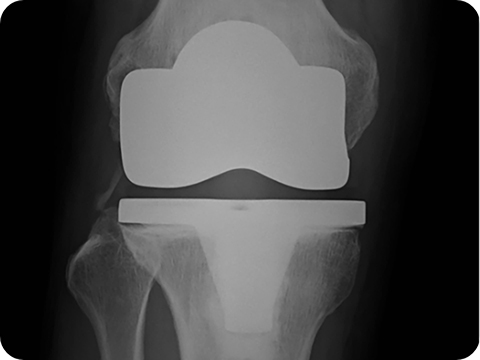

人工膝関節の手術は、膝関節の前面に切開を加え、大腿骨・脛骨・膝蓋骨を人工膝関節の形状に合わせて骨切りを行ない、金属・ポリエチレンなどで関節面の置換を行ないます。